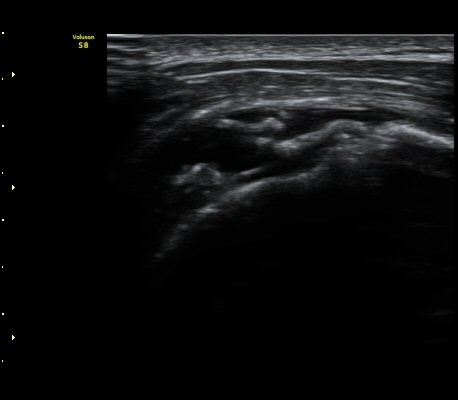

±Ø»ó°Ç Á¾´Ü¸é°Ë»ç¿¡¼­ ±Ø»ó°ÇÀÇ ÀüÃþÆÄ¿­°ú ±Ø»ó°ÇÀ» ¿¬°áÇÑ ºÀÇջ簡 Á÷¼± À¸·Î °üÂûµÈ´Ù(»çÁø 3, 4)

ÀϺΠ±Ø»ó°Ç Á¾´Ü¸é°Ë»ç¿¡¼­ ±Ø»ó°ÇÀÇ ÀüÃþÆÄ¿­°ú ±Ø»ó°Ç¸¦ ¿¬°áÇÑ ºÀÇջ簡 ±¸ºÒ±¸ºÒ(tortous)ÇϰÔ

°üÂûµÇ¾î ºÀÇÕ»ç ÆÄ¿­À» ½Ã»çÇÑ´Ù(»çÁø 5, 6).